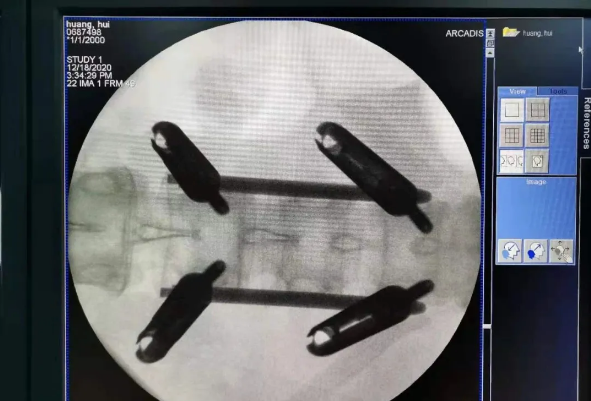

由于天璣?骨科手術機器人的精準及高效,可以使手術時間明顯縮短,因此在骨盆骨折手術后,在廖琦教授指導下,脊柱外科團隊利用天璣?骨科手術機器人同樣為20歲女性腰椎骨折患者“量身定做”最理想、最安全的教科書般的通道,完美安全微創完成手術,手術不僅時間縮短,并且出血和透視減少。

我國自主研發的天璣?骨科手術機器人,是針對骨骼硬組織的先進技術,已經獲得國際認可,能夠開展脊柱全節段 (頸椎、胸椎、腰椎、骶椎) 疾病、骨盆和四肢等骨折、骨腫瘤以及關節導航等手術。相比傳統手術,機器人輔助手術具有手術創傷小、出血少、并發癥少、康復快的優勢。同時,由于不需通過反復透視來確定置釘位置,從而能減少術中輻射,大大降低患者輻射危害,且手術過程中,由機器人與主刀醫師共同完成手術,大大增加了手術安全性。

在南昌市第一醫院廖琦教授帶領下,由創傷骨科團隊借助天璣?骨科手術機器人為患者“量身定做”最理想、最安全的教科書般的通道,完美安全微創完成手術,并且手術時間明顯縮短,真正做到“指哪兒打哪兒”!更讓患者放心的是,天璣?骨科手術機器人的“穩定手”機械臂進行精準定位,不用反復探尋。